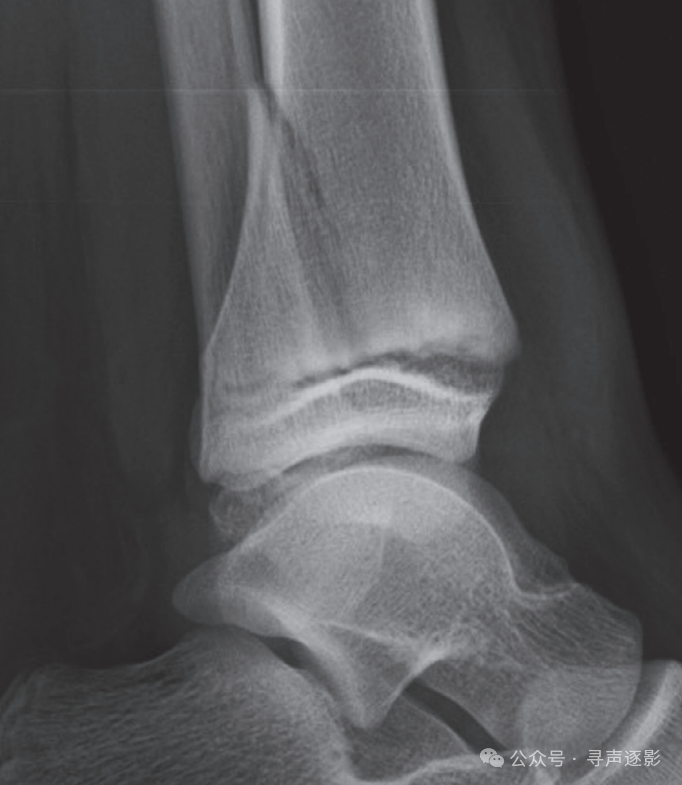

正常踝关节(左,成人;右,儿童)正位 Mortise片

正常踝关节侧位片